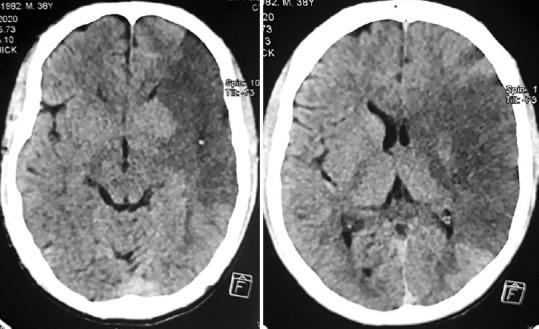

Left ventricular (LV) thrombus is a known complication of acute myocardial infarction (AMI), especially anterior wall MI and leads to systemic thromboembolism. However, increase in the rates of coronary perfusion either by thrombolysis or percutaneous interventions have reduced its incidence. Concurrent stroke and MI are seen in 0.009% of cases. The occurrence of AMI with LV thrombus with or without stroke mandates the combination of antiplatelet and antithrombotic therapy. Hitherto, there are no randomized studies in the setting of AMI with LV thrombus comparing dual (single antiplatelet plus oral anticoagulant [OAC]) and triple therapy (dual antiplatelet therapy with OAC). There are no large randomized trials as well to delineate the optimal therapy for simultaneous cardiac and cerebral infarction. We hereby, report an unusual case of a young patient who presented with triple combo of acute anterior wall MI, LV thrombus, and ischemic stroke and discuss the challenges in management in this scenario.